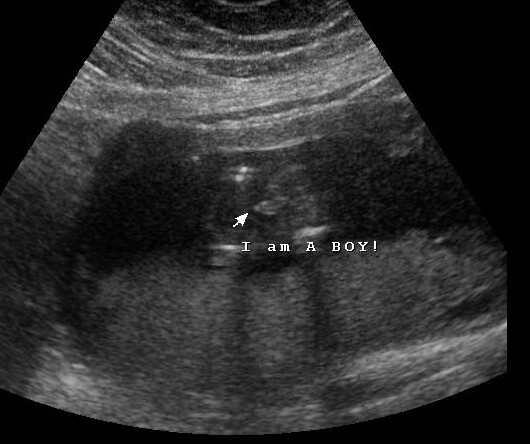

Hello, longtime lurker and nubsesser, first time poster here! Had my 12.2 week NT scan and asked for nub pics but tech didn't know about it. I tried to explain and at end of scan she gave me these shots including potty shots which I know are unreliable but I can't seem to find any to compare what I'm seeing. Any thoughts/opinions about what's showing in any pic is welcome! Thanks so much!

Attachment 29906Attachment 29905Attachment 29903Attachment 29904